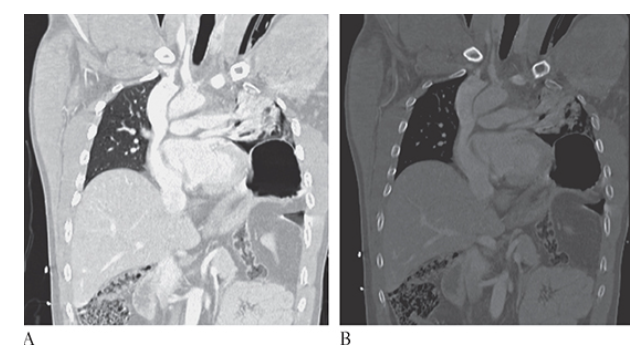

What is A

Lung Contusion. CECT axial coronal MPR

What is B

Lung Contusion. CECT axial and sagittal MPR

What is C

Lung Contusion. CECT axial images of a trauma patient showing the extensive pulmonary contusion of the right upper and lower lobes. There is confluent lung opacification with multiple small posttraumatic pneumatoceles.